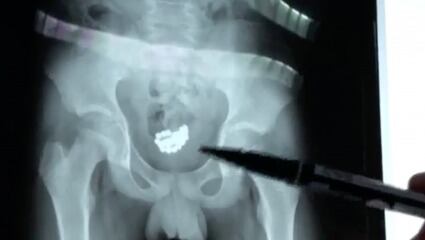

A un niño de 13 años en el norte de China se le extrajeron 29 bolitas magnéticas de la vejiga después de insertarlas en su pene.

En otro clip, un médico también mostró las 29 cuentas magnéticas a la cámara después de haber sido retiradas del niño a través de la cirugía.

Según los informes, el niño curioso insertó las cuentas magnéticas en su pene y no las sacó.

Finalmente, los médicos retiraron las 29 bolas magnéticas de su cuerpo y él continúa recuperándose en casa. Video: Reuters.